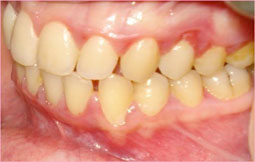

Examen clinique : (fig. 1.2.3.)

Le premier élément à constater après ouverture buccale, est l’hygiène très faible de la patiente avec la présence d’importants dépôts de plaque et de tartre. L’indice de plaque a été estimé à 2,37 alors que l’indice gingival de Silness et Loe était de 2,5.

La gencive est d’aspect inflammatoire, turgescente, saignante au moindre contact, avec présence de diastème et de récession papillaire entre 12 et 11 (fig 1, 2).

Sur le plan dentaire, on note la présence des caries occlusales superficielles sur 16, 26, 27, 34, 36, 46, 47 avec égression de la 11.